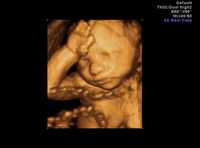

Imagen tridimensional de un feto de 23 semanas

Grupos pro vida buscan reducir en Gran Bretaña el límite de 24 semanas para abortar

Londres, 5 de mayo. Aunque el aborto se legalizó hace 40 años en Gran Bretaña, los activistas por el derecho a la libre elección dicen que los avances logrados con esfuerzo están ahora bajo la presión de grupos que intentan bajar el límite de 24 semanas para la interrupción del embarazo.